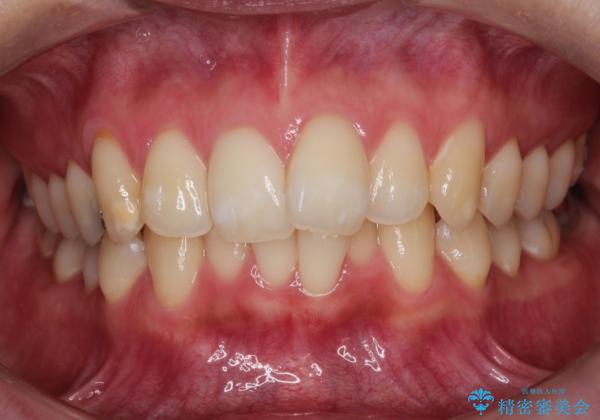

奥歯の噛み合わせは整っていたため、前歯の並びを美しく修正することに専念できました。マウスピース矯正による治療で短期間で改善しました。

前歯のガタツキを改善する治療法として、マウスピース矯正が適していることが多いです。

マウスピース矯正は、金属製のブラケットやワイヤーを使用せずに、透明なマウスピースを装着して歯を移動させる方法です。そのため、目立たず、痛みも少ないです。